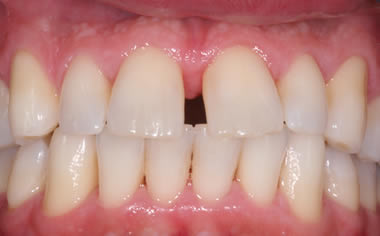

Case Three (2 images)

Treatment of moderate gum disease.